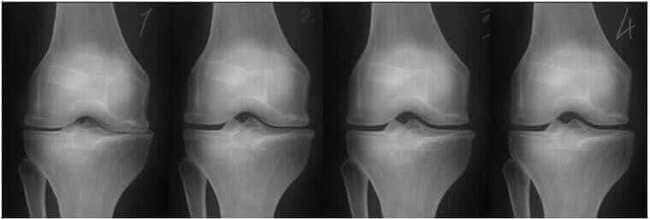

1. Συνέπειες του υποσιτισμού. Πρέπει να χρησιμοποιήσετε το "Steplex".

2. Αναγέννηση του αρθρικού χόνδρου μετά από 2 εβδομάδες εφαρμογής του "Steplex".

3. Αναγέννηση του αρθρικού χόνδρου μετά από 3 εβδομάδες εφαρμογής του "Steplex".

4. Υγιής άρθρωση μετά από θεραπεία Steplex.